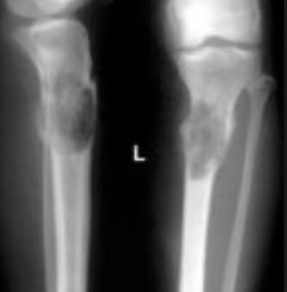

Osteochondromas are most commonly found in the metaphysis of long bones; most commonly the femur or proximal tibia.

X-rays of an osteochondroma show bone mass growing out from the metaphyseal region. MRI can distinguish malignancy, which is determined when the bone mass is not continuous with the normal cancellous bone.